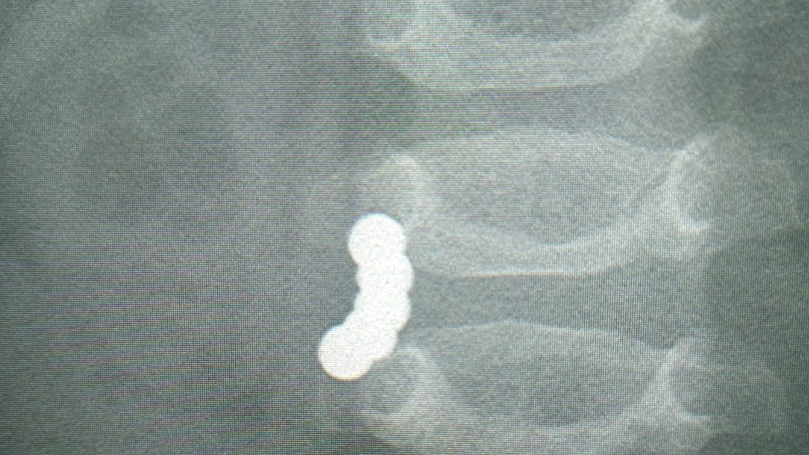

Годовалый томич поступил в БСМП №2 в июле. В ходе обследований в кишечнике ребенка были обнаружены пять магнитных шариков из популярной игрушки-конструктора. Медики диагностировали перфорацию – сквозное повреждение стенки кишечника, при котором содержимое органа попадает в брюшную полость.

«У ребенка было шесть дырок в кишечнике - такая степень повреждения органа равносильна прямому выстрелу дробью в область живота. Хирурги экстренно прооперировали малыша, извлекли магниты и ушли перфорации», – отметил главный врач БСМП №2 Андрей Караваев.Однако содержимое кишечника, попавшее внутрь брюшной полости, успело вызвать у ребенка перитонит – острое воспаление. Сейчас он находится в реанимации, ему предстоит длительное лечение и восстановление. Врач добавил, что попадание в кишечник детей магнитных шариков - распространенная проблема не только в Томске, но в России в целом.